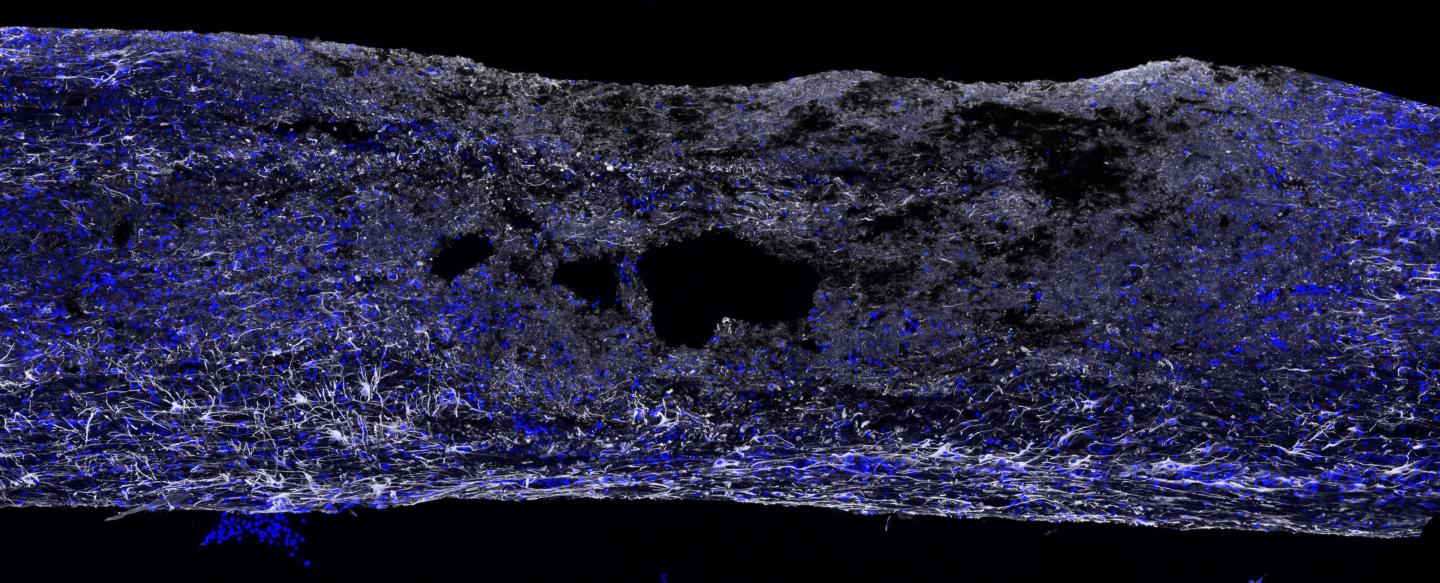

CHARLOTTESVILLE, Va., Dec. 19, 2016 - A rare and powerful type of immune cell has been discovered in the meninges around the brain, suggesting the cells may play a critical but previously unappreciated role in battling Alzheimer's, multiple sclerosis, meningitis and other neurological diseases, in addition to supporting our healthy mental functioning. By harnessing the cells' power, doctors may be able to develop new treatments for neurological diseases, traumatic brain injury and spinal cord injuries - even migraines.

The cells, known as "type 2 innate lymphocytes," previously have been found in the gut, lung and skin - the body's barriers to disease. Their discovery in the meninges, the membranes surrounding the brain, comes as a surprise. They were found as UVA researcher Jonathan Kipnis, PhD, explored the implications of his lab's game-changing discovery last year that the brain and the immune system are directly connected via vessels long thought not to exist

Curiously, the immune cells were found along the vessels discovered by Kipnis' team. "They're right on the lymphatics, which is really weird," noted researcher Sachin Gadani. "You have the lymphatics and they're stacked right on top. They're not inside of them - they're around them."